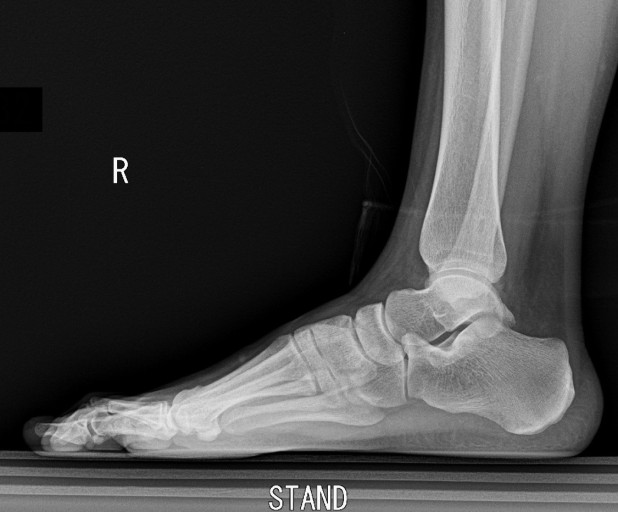

초기에는 밤에만 불편함을 느끼다가 점점 지속 시간도 늘어납니다.3. 족저근막염

발바닥 통증의 대표 질환으로,

발뒤꿈치에서 발바닥 전체로 이어지는 근막에 염증이 생기며

걷거나 서 있을 때 발바닥이 뜨겁고 찌릿한 통증을 유발합니다.

특히 아침에 첫 발을 디딜 때 더 아픈 경우가 많아요.